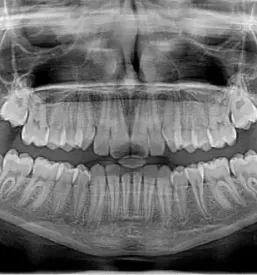

Zavedamo se pomena preventive, zato izvajamo higienske terapije, ki obsegajo:

- odstranjevanje mehkih in trdih zobnih oblog

- peskanje zob

- poliranje zob

- svetovanje glede ustne higiene doma